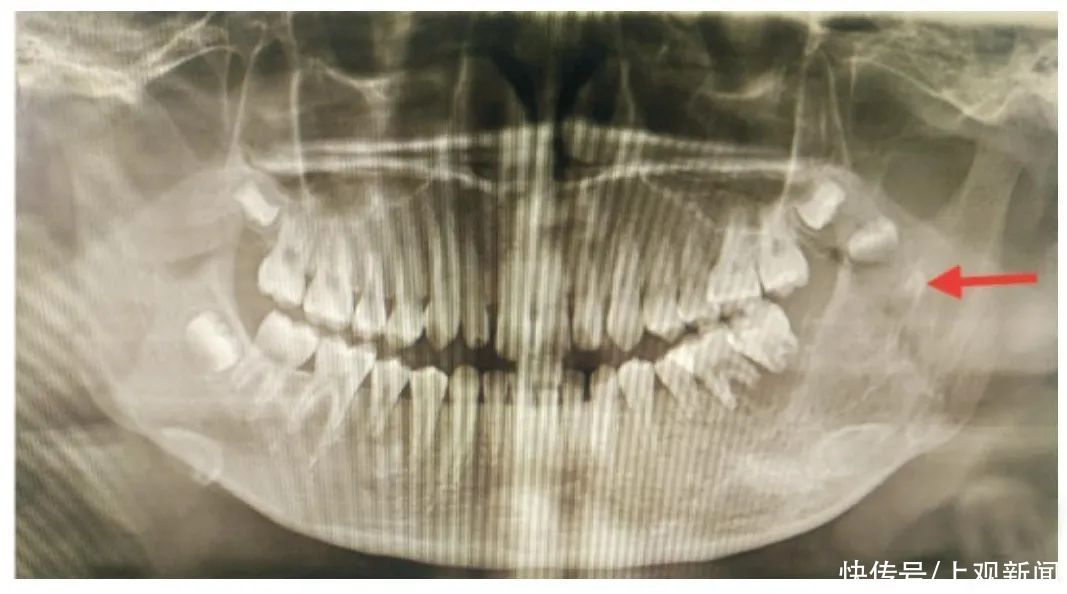

前段时间,一个五岁女童拔牙后出血不止,甚至被送进ICU病房,终被鉴定为脑死亡,引发众多网友关注。